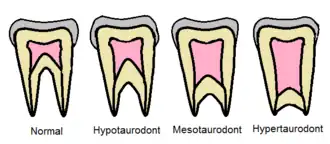

Dabei handelt es sich um eine abnormale Form des Zahnes mit vergrößerter Zahnpulpa, Verlagerung der Bifurkation in Richtung Wurzelspitze, fehlende Taille am Zahnhals aufgrund einer Fehlentwicklung der Hertwig-Epithelscheide.[6]

Eine Einteilung in

- milde Form (Hypotaurodontismus)

- mäßig ausgeprägte Form (Mesotaurodontismus)

- ausgeprägte Form (Hypertaurodontismus)

wurde im Jahre 1928 von C. Shaw vorgeschlagen.[7]